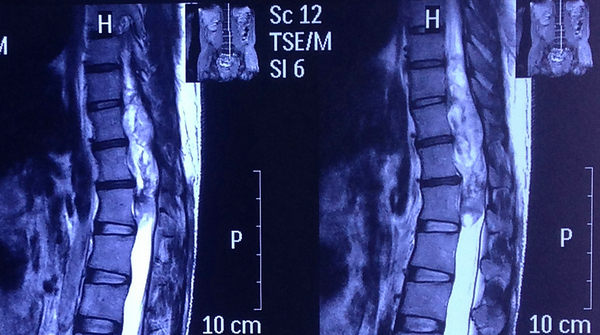

患者肖某,中年男性,20余年来腰部疼痛及双下肢疼痛、无力,后逐渐进展为行走困难,双下肢肌肉萎缩,排便障碍。肖某以为自己得了腰椎疾病便到某骨科医院就诊,然而核磁共振的检查结果却如同晴天霹雳:原来患者胸腰段脊髓内长了一个十五厘米的巨大肿瘤!而且肿瘤直接压迫脊髓和脊神经,肿瘤体积巨大,手术难度高,风险大,稍有不慎,则会有双下肢瘫痪、大小便失禁的可能。肖某辗转多家医院,均因手术难度过高而被婉拒,当地医生建议他去郑州大学五附院找河南省神经疾病会诊中心首席专家——王新军教授。

椎管巨大肿瘤